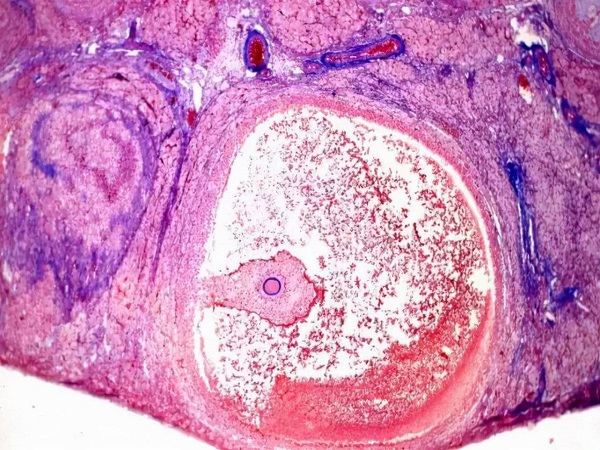

大家都知道,卵巢是女性生育和保持青春的重要器官,同时承担着分泌体内重要激素的作用。在女性的卵巢中有成千上万的卵泡,在不同的时期中卵泡会不断的生长发育直到成熟。正常情况下,女性卵巢中的卵泡数量应该是5-12个左右,过多过少的卵泡都会对女性的身体健康和生育造成影响,卵巢中只有两个卵泡是不正常的,有卵巢早衰的风险,建议及时进行治疗。

众所周知,女性卵巢中的卵泡数量会随着年龄的不断增长而变化,女性的年龄越大卵巢功能就越差,卵泡的数量也会随之减少。针对育龄期的女性来说,单侧卵巢中的卵泡数量应该是在3-11个左右的,低于3个或者是高于11个的就都属于异常情况。如果卵巢中只有两个卵泡的话也是不正常的,需要及时进行检查和治疗。不同阶段的女性卵巢中的卵泡数量是不同的,下面就为大家详细介绍一下。

1女性青春期:青春期的女性卵巢中的卵泡数量是非常多的,大概是有20-30万个左右,但是每个月也只会有一个卵泡生长发育成熟然后排出体外; 2育龄期:育龄期的女性左右两侧卵巢的卵泡数量应该是在10个左右的,通常也会有1-2个发育成熟,其他的就会萎缩,如果卵泡数量低于3个的话就说明有卵巢早衰的可能; 3围经期:在围经期的时候女性卵巢中的卵泡数量就会逐渐减少,一般在3-5个之间是比较正常的,低于这个范围也属于异常情况要及时进行检查。